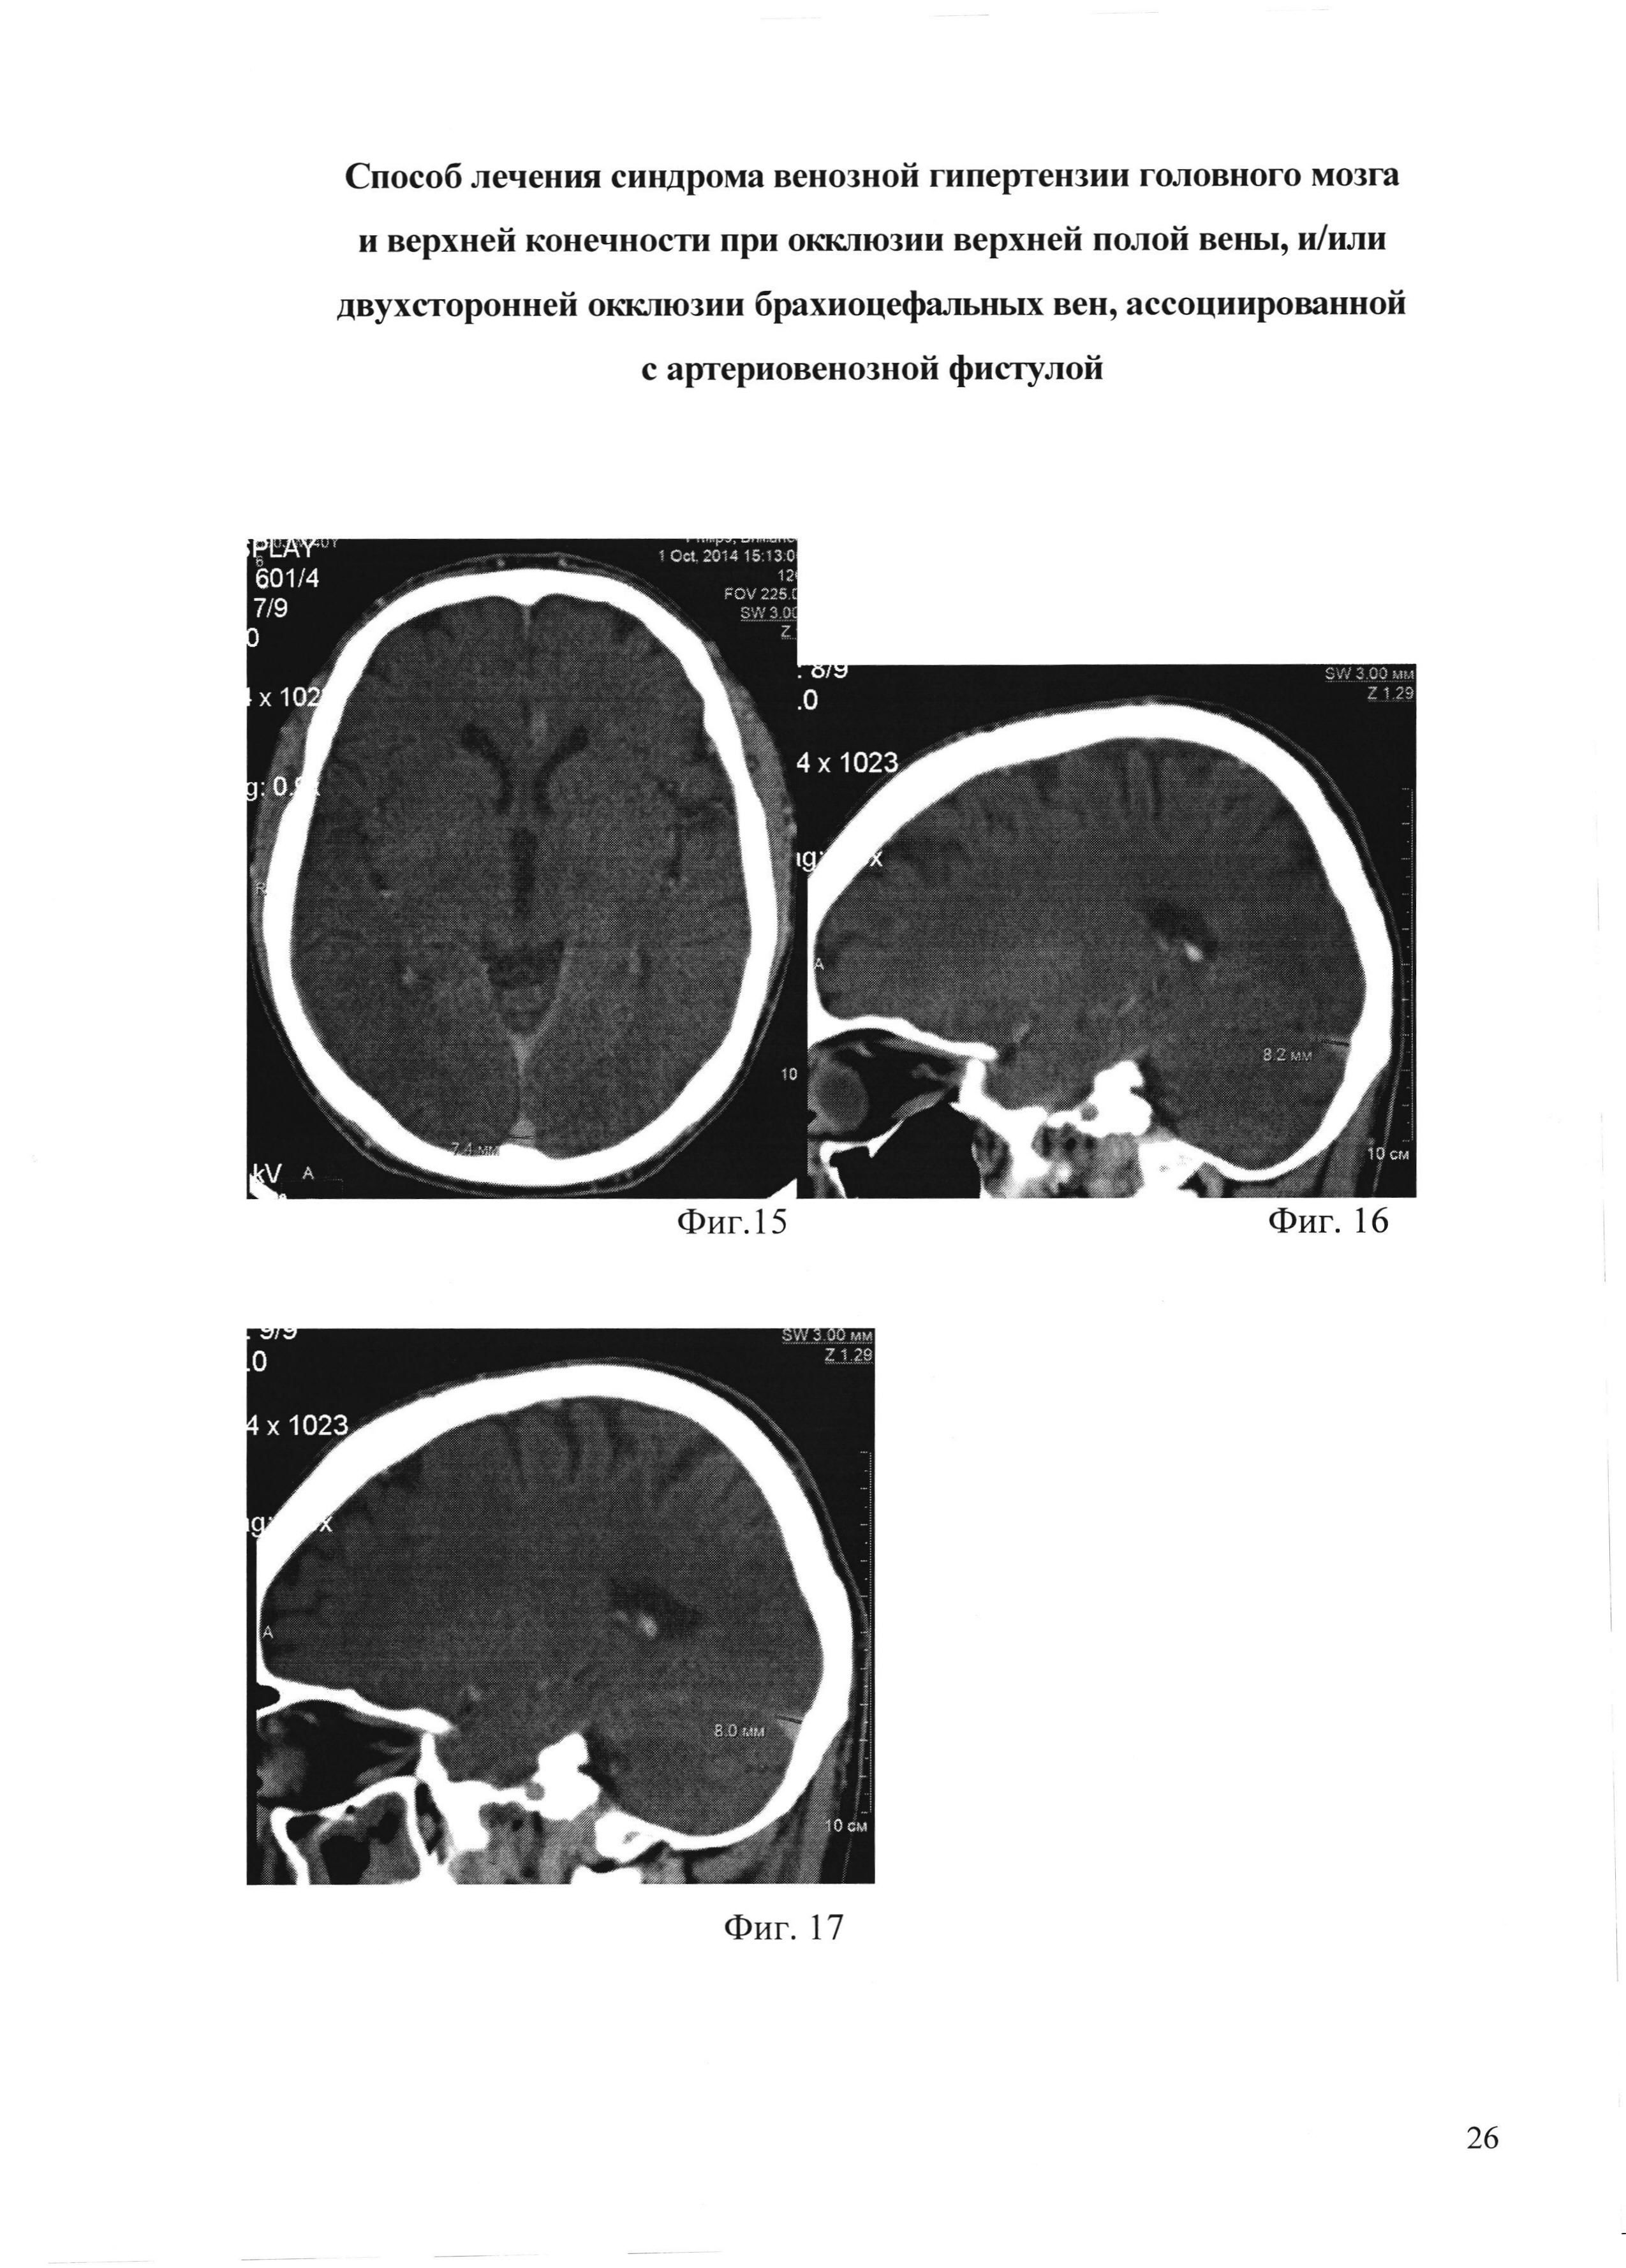

На фиг. 15 - фиг. 17 приведена рентгеновская компьютерная томография головного мозга, с контрастированием, пациента М., через 60 дней после операции:

[43]

На фиг. 15 - сагиттальный синус;

[44]

На фиг. 16 - поперечный синус справа;

[45]

На фиг. 17 - поперечный синус слева.

Через 60 дней после операции: отека лица, шеи, плечевого пояса и левой руки нет (фиг. 11-фиг. 13). Объем левой руки уменьшился на 1310 мл. По данным флебографии (фиг. 14) шунт функционирует, весь объем крови из артериовенозной фистулы идет по протезу в сафено-феморальное соустье с дальнейшим контрастированием общей бедренной вены, подвздошных вен и нижней полой вены. Мышечная сила и чувствительность в левой руке вернулись к нормальным показателям. По данным теста MMSE - когнитивных нарушений нет (29 баллов), по модифицированной шкале Рэнкина - незначительное уменьшение дееспособности (1 степень). Индекс мобильности Ривермид составляет 14 баллов, тест качества жизни по шкале DASH - 10,8 баллов. По данным ТКДГ ЛСК по вене Розенталя справа - 15 см/сек, слева - 17 см/сек, по внутренней яремной вене антеградный кровоток. По данным РКТ головного мозга (фиг. 15-17): уменьшение поперечных и сагиттальных синусов: ширина сагиттального синуса 7,4 мм, поперечного синуса справа 8,2 мм, слева 8 мм.